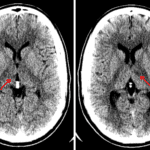

- Small areas of hypoattenuation in both thalami

- Artery of Percheron infarct

Small areas of hypoattenuation in both thalami represent age-indeterminate infarcts. Recommend brain MRI for further evaluation. No evidence of acute hemorrhage, mass effect, or hydrocephalus.